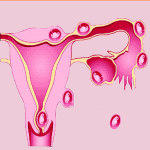

Thai Ngoài Tử Cung | Bài giảng CĐHA

Thai ngoài tử cung (Ectopic Pregnancy) là hiện tượng làm tổ của trứng đã thụ tinh ngoài buồng tử cung. 95% thai ngoài tử cung vị trí ở vòi trứng, trong đó 70% ở 2/3 ngoài. Số còn lại ở các vị trí: cổ tử cung, buồng trứng, trong ổ bụng. Sự phát triển của thai ở những vị trí bất thường này sẽ gây nên hiện tượng xuất huyết, hoại tử, có thể làm vỡ vòi trứng và gây nên xuất huyết nội…